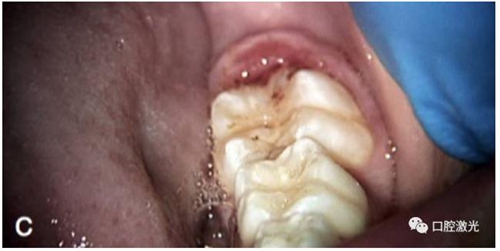

術(shù)中

術(shù)后即刻